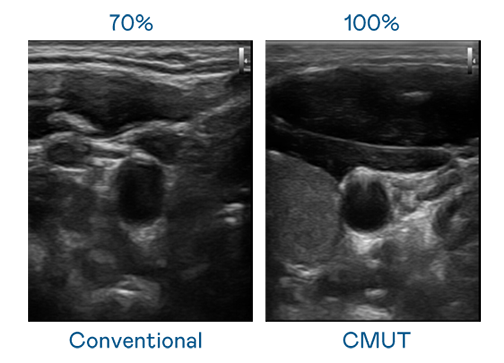

CMUT 技术是一种用电容式微机电元件来产生超音波讯号的技术。与传统 PZT 压电式技术相比,CMUT 频宽增加 30%,更宽频的超音波讯号让影像解析度大幅提升,是实现高影像品质医疗超音波扫描、促进精准医疗发展的关键技术。

大频宽带来超清晰影像

超音波影像的解析度高低,首先取决于探头能发出的讯号频宽。伟德国际1949 CMUT 可提供高清晰的超音波讯号,提供高频宽、高灵敏度、影像纹理细节更高的超音波影像,协助医护人员缩短影像判读时间及利用精准的医疗影像进行诊断。